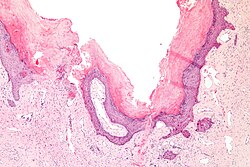

A. Inner labial biopsy shows subepithelial hyalinized pink/red material, about blood vessels and in general. B. The particularly glassy appearance of the material in areas is evident at high power.